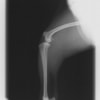

術前左後肢側面像

術後左後肢側面像

手術前後のTPA(脛骨高平部の角度)を測定しています。

約29°から約10°へ矯正されています。

術前のTPAは左後肢33.1°右後肢26.8°でしたがTPLO実施により左後肢5.5°右後肢12°に矯正されました。